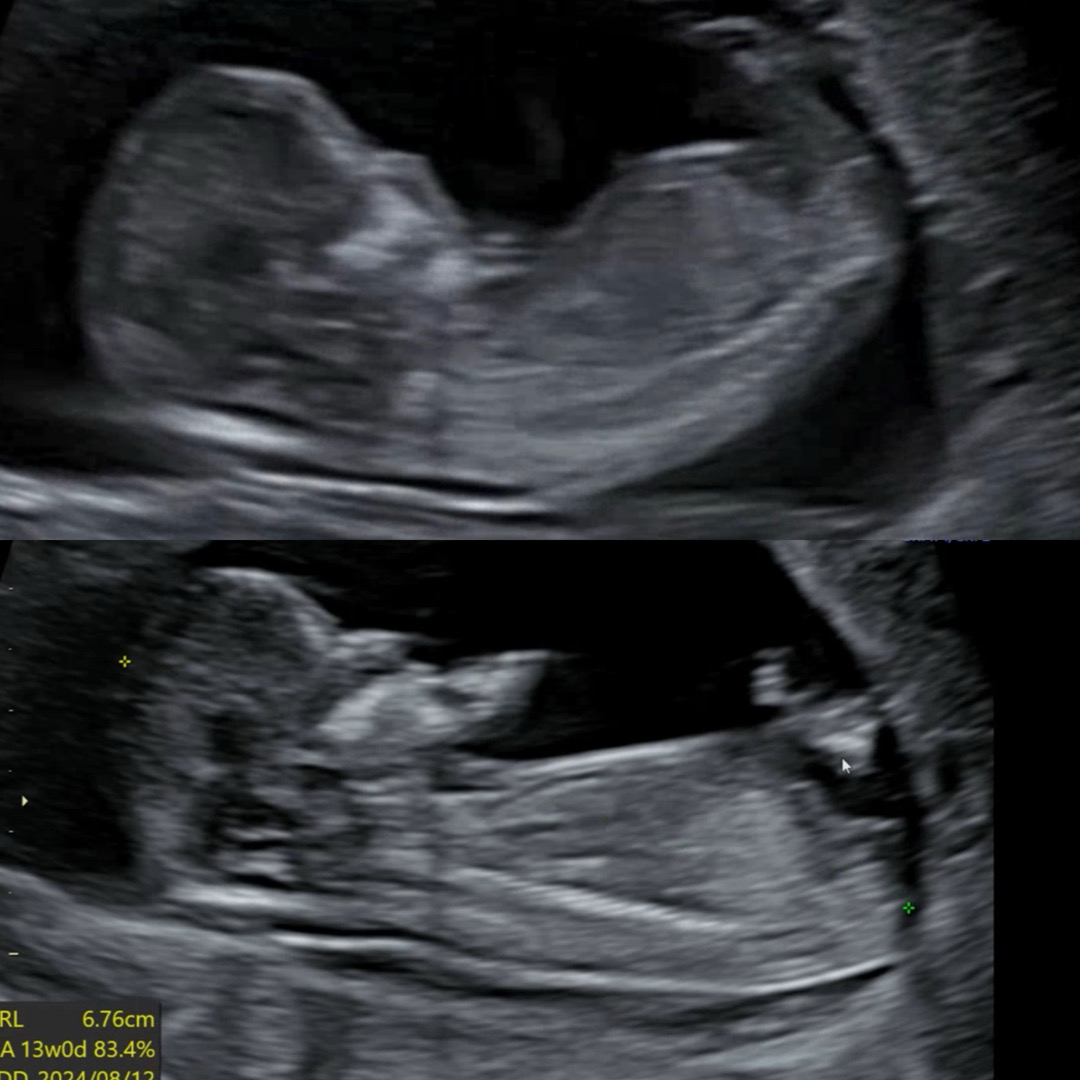

12주 각도법 봐주실수 있으실까요!

동영상을 아무리 돌려봐도,, 제가 잘 캡쳐한건지도 모르겠습니다ㅠㅠ 조언 부탁드려요!🩵